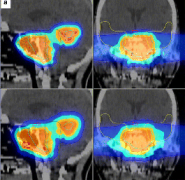

脑膜瘤 作为颅内肿瘤,由于生长在脑膜及脑膜间隙,在治疗方面很多患者都不愿意手术治疗,怕风险太大或是会引起并发症,那么不做手术还有什么新疗法能治这一疾病吗?质子治疗的...